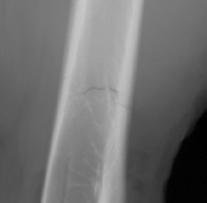

X-ray exposure of a bone fracture (right).